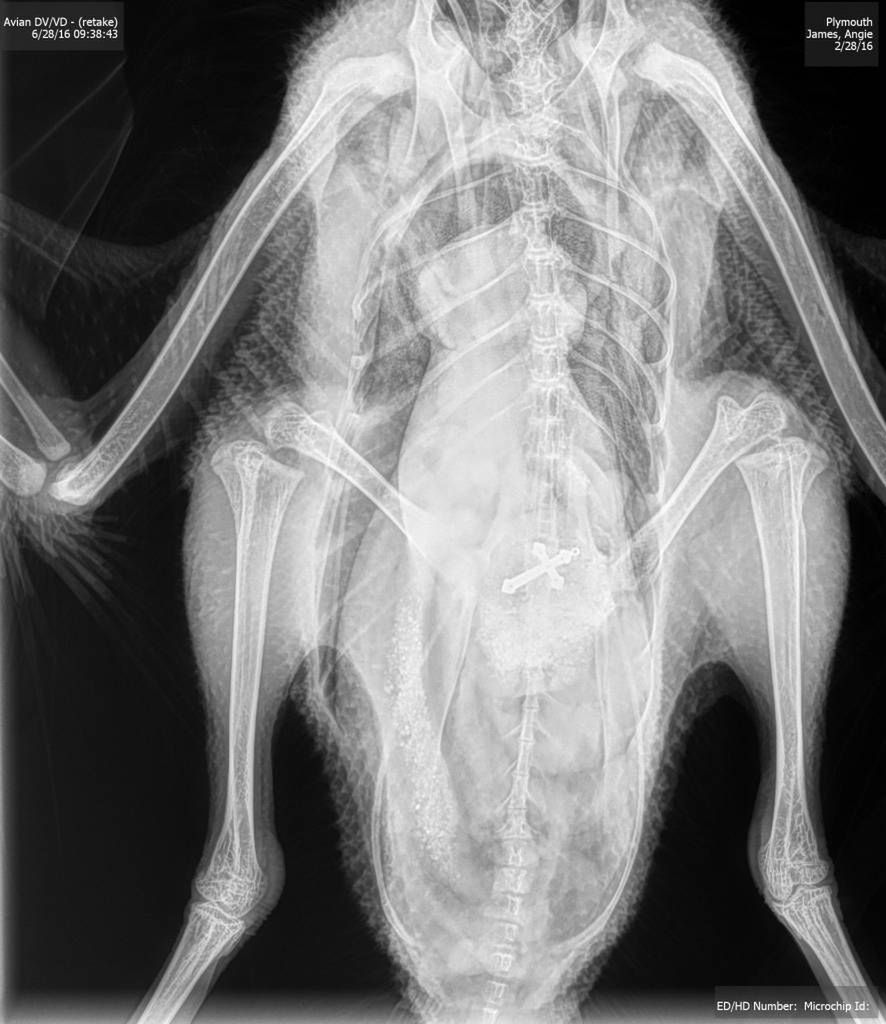

/ 11Co zjadła?

Obraz

© Veterinary Practice News/Lauren Flanagan, DVM, of Pepperell Veterinary Hospital in Pepperell, Mass.

Zwyciężyła półroczna angielska buldożka Leia. Właściciel dał jej do obgryzania 12-cm kość. Nie przewidział, że suczka połknie ją w całości.